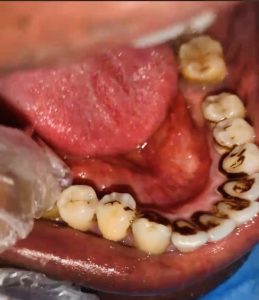

- Dental Caries (Tooth Decay)

Dental caries occurs when dental plaque on tooth surfaces breaks down free sugars, including sugar added during food processing or naturally present in honey, syrups, and fruit juices into acids. These acids gradually erode tooth enamel, leading to cavities.

High sugar intake, poor plaque removal, and inadequate fluoride exposure significantly increase the risk of caries, which can result in pain, infection, and tooth loss if left untreated.

- Periodontal (Gum) Disease

Periodontal disease damages the tissues supporting the teeth and is characterized by symptoms such as swollen or bleeding gums, pain, and bad breath. In severe cases, the gum can separate from the tooth, and the underlying bone may deteriorate, causing tooth mobility or eventual tooth loss.

Severe periodontal disease affects over 1 billion people worldwide, with poor oral hygiene and tobacco use as major risk factors.

The most common identified dental conditions affecting Nigerians include tooth decay, gum disease, tooth sensitivity, and persistent bad breath. This issue is further compounded by Nigeria’s dietary culture, which is rich in starchy and sugary foods that promote cavities.

Bacteria in the mouth feed on sugars, producing acid that erodes tooth enamel, causing cavities. Frequent consumption of acidic substances can wear away tooth enamel, leading to tooth erosion.

Tooth enamel erosion is a condition that develops very slowly and leaves teeth both discolored and rounded-looking. Its primary cause is consuming plenty of sugary and acidic foods such as soda and sweets over a long period of time.